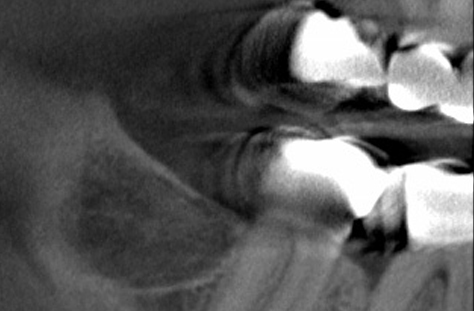

NICO

Unter NICO (Neuralgia inducing cavitational osteonecrosis) versteht man chronisch entzündliche Bereiche im Kieferknochen.

DVT 3D-Diagnostik

In unserer Praxis nutzen wir die dreidimensionale Röntgendiagnostik (DVT) im Vorfeld jeder Implantation und Störfeldsanierung.